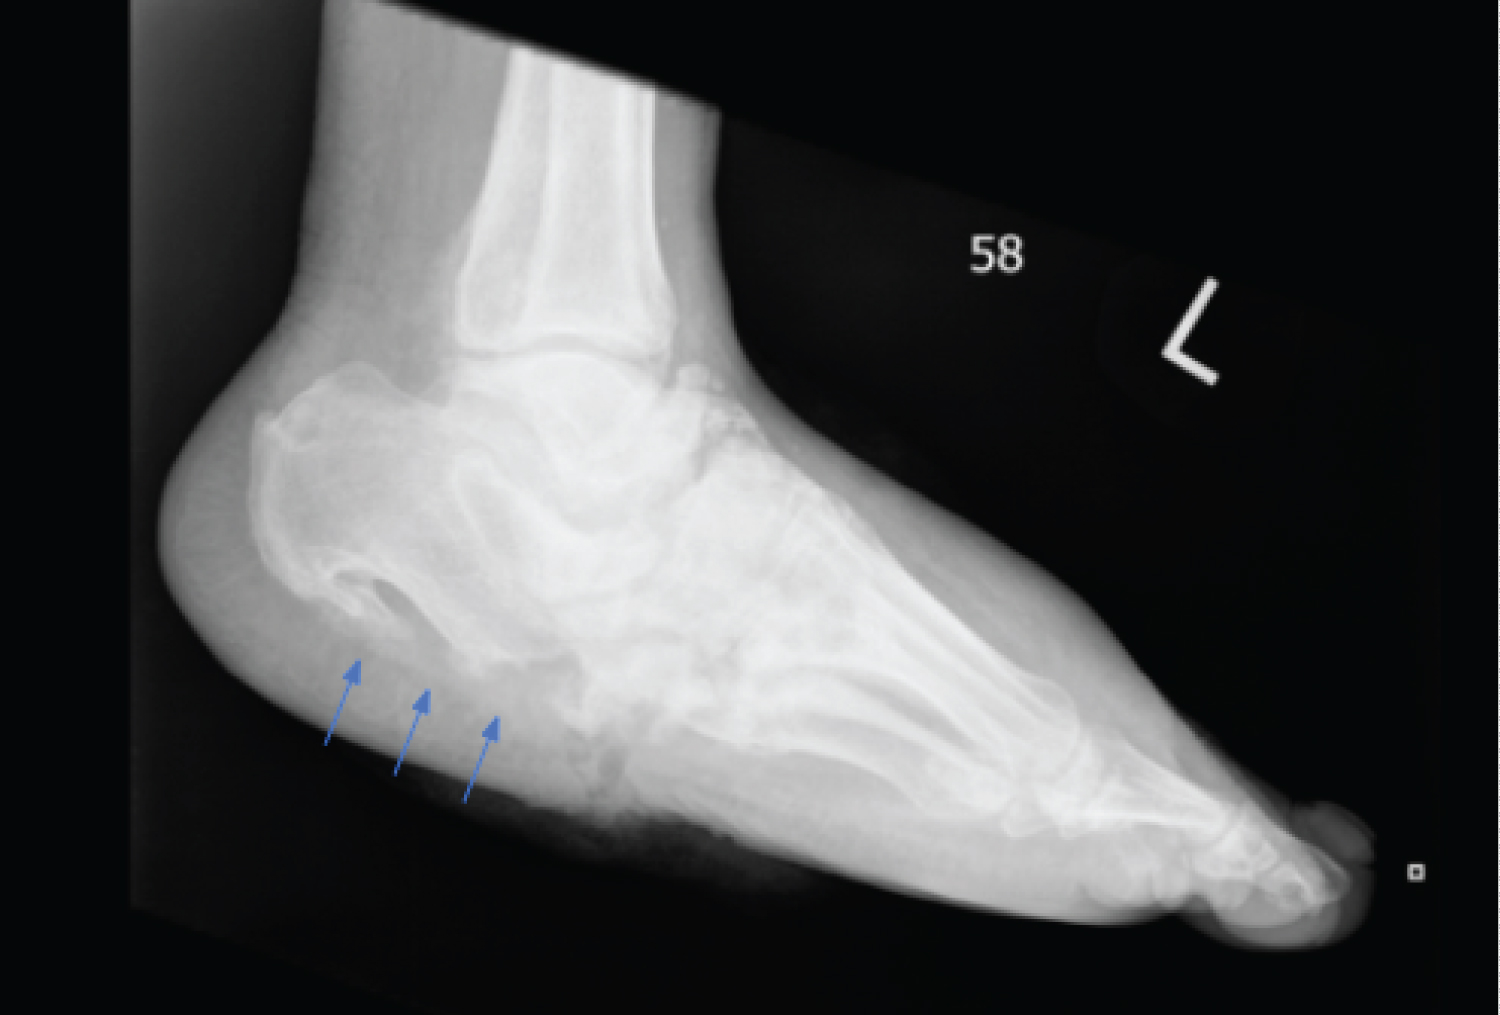

The cortex was defined as "intact" if the plantar aspect of the calcaneus had visible uniform bone on radiograph. The cortex was absent of fracturing and cortical dissolution (Figure 1). The cortex was deemed "not-intact" if the plantar calcaneal cortex had radiographically visible fracturing or fragmentation of the cortical bone (Figure 2). If there was discrepancy between the two independent physicians, a third physician (NC) evaluated the radiographs to determine if the plantar calcaneal cortex was intact.

Figure 1: Example radiograph of a patient with Charcot destructive processes with an intact calcaneal cortices. Arrows indicate undisrupted plantar calcaneal cotices. View Figure 1

Figure 2: Example radiograph of Charcot destructive processes with a fractured calcaneal cortices. Arrows indicate disruption in plantar calcaneal cotices. View Figure 2